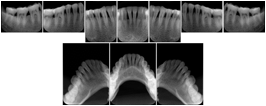

In most standard cases, images are oriented in structured layouts. These structured displays are useful to be shared between providers for reference purposes.

Table OO.1.1-1 shows structured display standard templates, where Viewset ID is based on the Japanese Society for Oral and Maxillofacial Radiology (JSOMR) classification provided by JIRA (Japan Medical Imaging and Radiological Systems Industries Association, www.jira-net.or.jp). Expected or typical teeth to be imaged location, region and designation codes are based on ISO 3950-2010, Dentistry - Designation system for teeth and areas of the oral cavity. For all the hanging protocols listed in OO.1.1-1, the value to use for Hanging Protocol Creator (0072,0008) is "JSOMR" and the value to use for Hanging Protocol Name (0072,0002) does not include "JSOMR" (e.g., "DL-S001A", not "JSOMR DL-S001A").

Table OO.1.1-1. Hanging Protocol Names for Dental Image Layout based on JSOMR classification